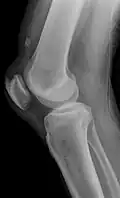

Quadriceps tendon rupture in plain X-ray

-

Quadriceps tendon rupture in plain X-ray: Incomplete rupture with haematoma in tendon.